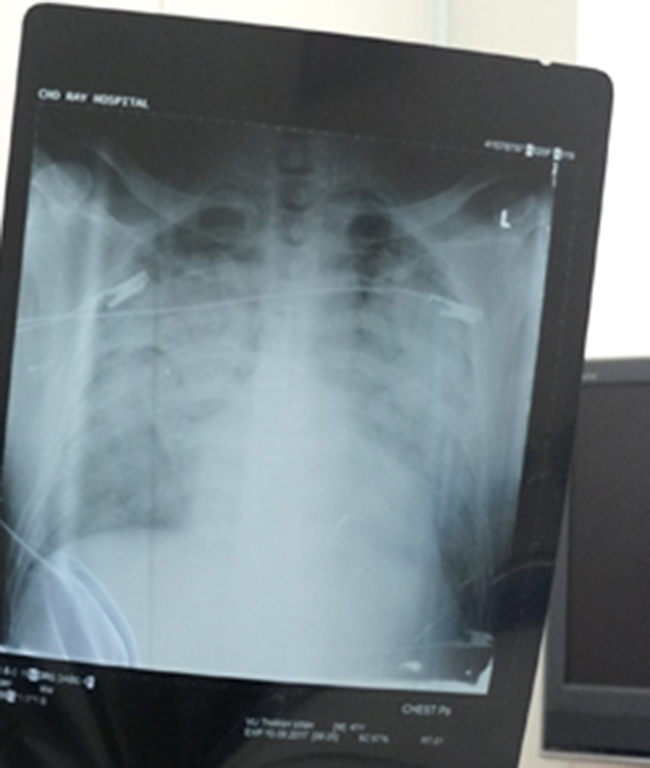

Tấm phim chụp phổi của bệnh nhân

Ngày 10/9, bệnh nhân được đưa lên khoa Hồi sức cấp cứu cùng chẩn đoán viêm phổi cộng đồng tiến triển nhanh, sốt cao, phổi trắng hai bên và hầu như không thở được...